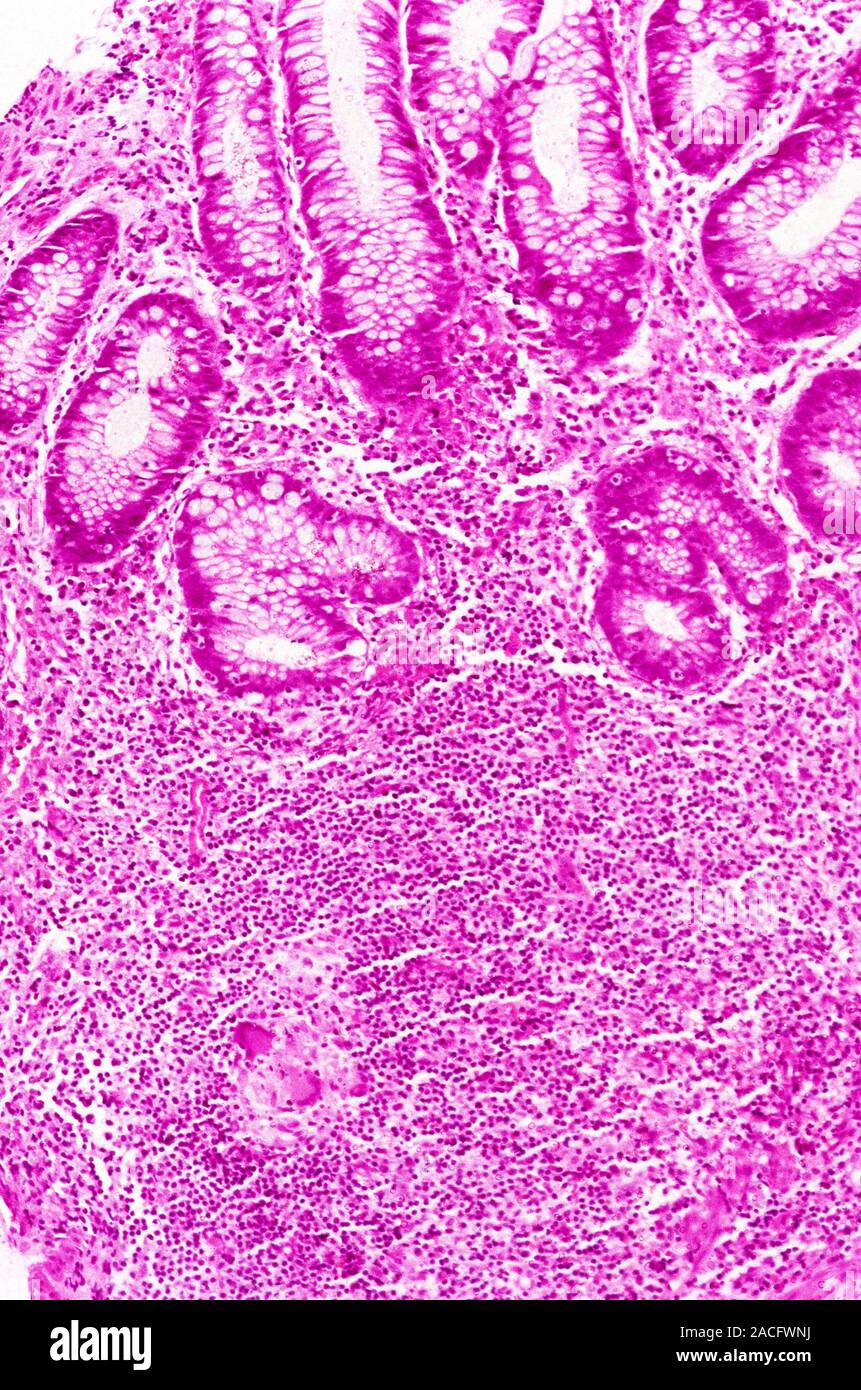

Light micrograph of a part of the wall of the human small intestine in Crohn's Disease Granuloma Granulomas create a protective barrier around bacteria or foreign. crohn's disease (cd) is diagnosed from information obtained clinically, pathologically, and. epithelioid granuloma is one hallmark used to histologically diagnose crohn's disease (cd). crohn’s disease (cd) is a chronic transmural inflammatory bowel disease of unknown etiology. However, the clinical significance of. the presence of granulomas in the. Crohn's Disease Granuloma.